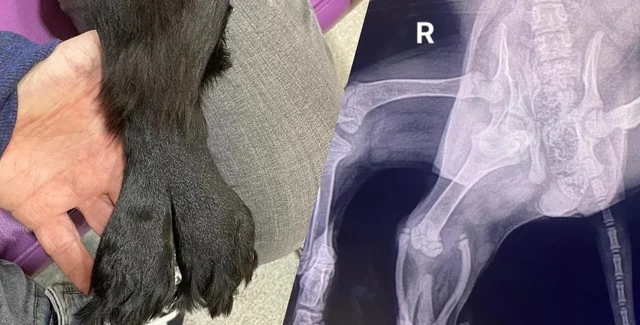

Дві додаткові кінцівки кокер-спанієля злилися разом, утворивши "хвіст русалки", але медики змогли їх видалити без шкоди тварині.

Цуценя кокер-спанієля народилося з множинними вродженими дефектами й було покинуте власниками у віці всього 11 тижнів. Серед вроджених дефектів тварини також були дві додаткові задні кінцівки, які зрослися та утворили щось на зразок "хвоста русалки", пише IFLScience.

На щастя, цуценя врятували й назвали Аріель на честь русалки. Тепер вона успішно перенесла операцію, внаслідок якої лікарі видалили дві зайві кінцівки. За словами засновника і менеджера Greenacres Rescue Майкі Лоулора, наявність двох тазостегнових суглобів з одного боку не дозволили тазу сформуватися належним чином. У результаті нормальна задня права нога тварини майже не мала мішечного тонусу.

Аріель виявили на автостоянці супермаркету в Уельсі в жовтні 2023 року. Ветеринари припускають, що її викинули у віці близько 11 тижнів. Після того як тварину врятували, її доправили до ветеринара, де також було виявлено додаткову вульву, дві додаткові зрощені ноги, комп'ютерна томографія також засвідчила, що у цуценяти відсутня права нирка.

Тоді ветеринари подумали, що зрощені ноги собаки нагадують хвіст русалки — звідси та з'явилося ім'я. Згодом виявилося, що додаткові ноги тварини не функціональні, а тому потрібна була операція.